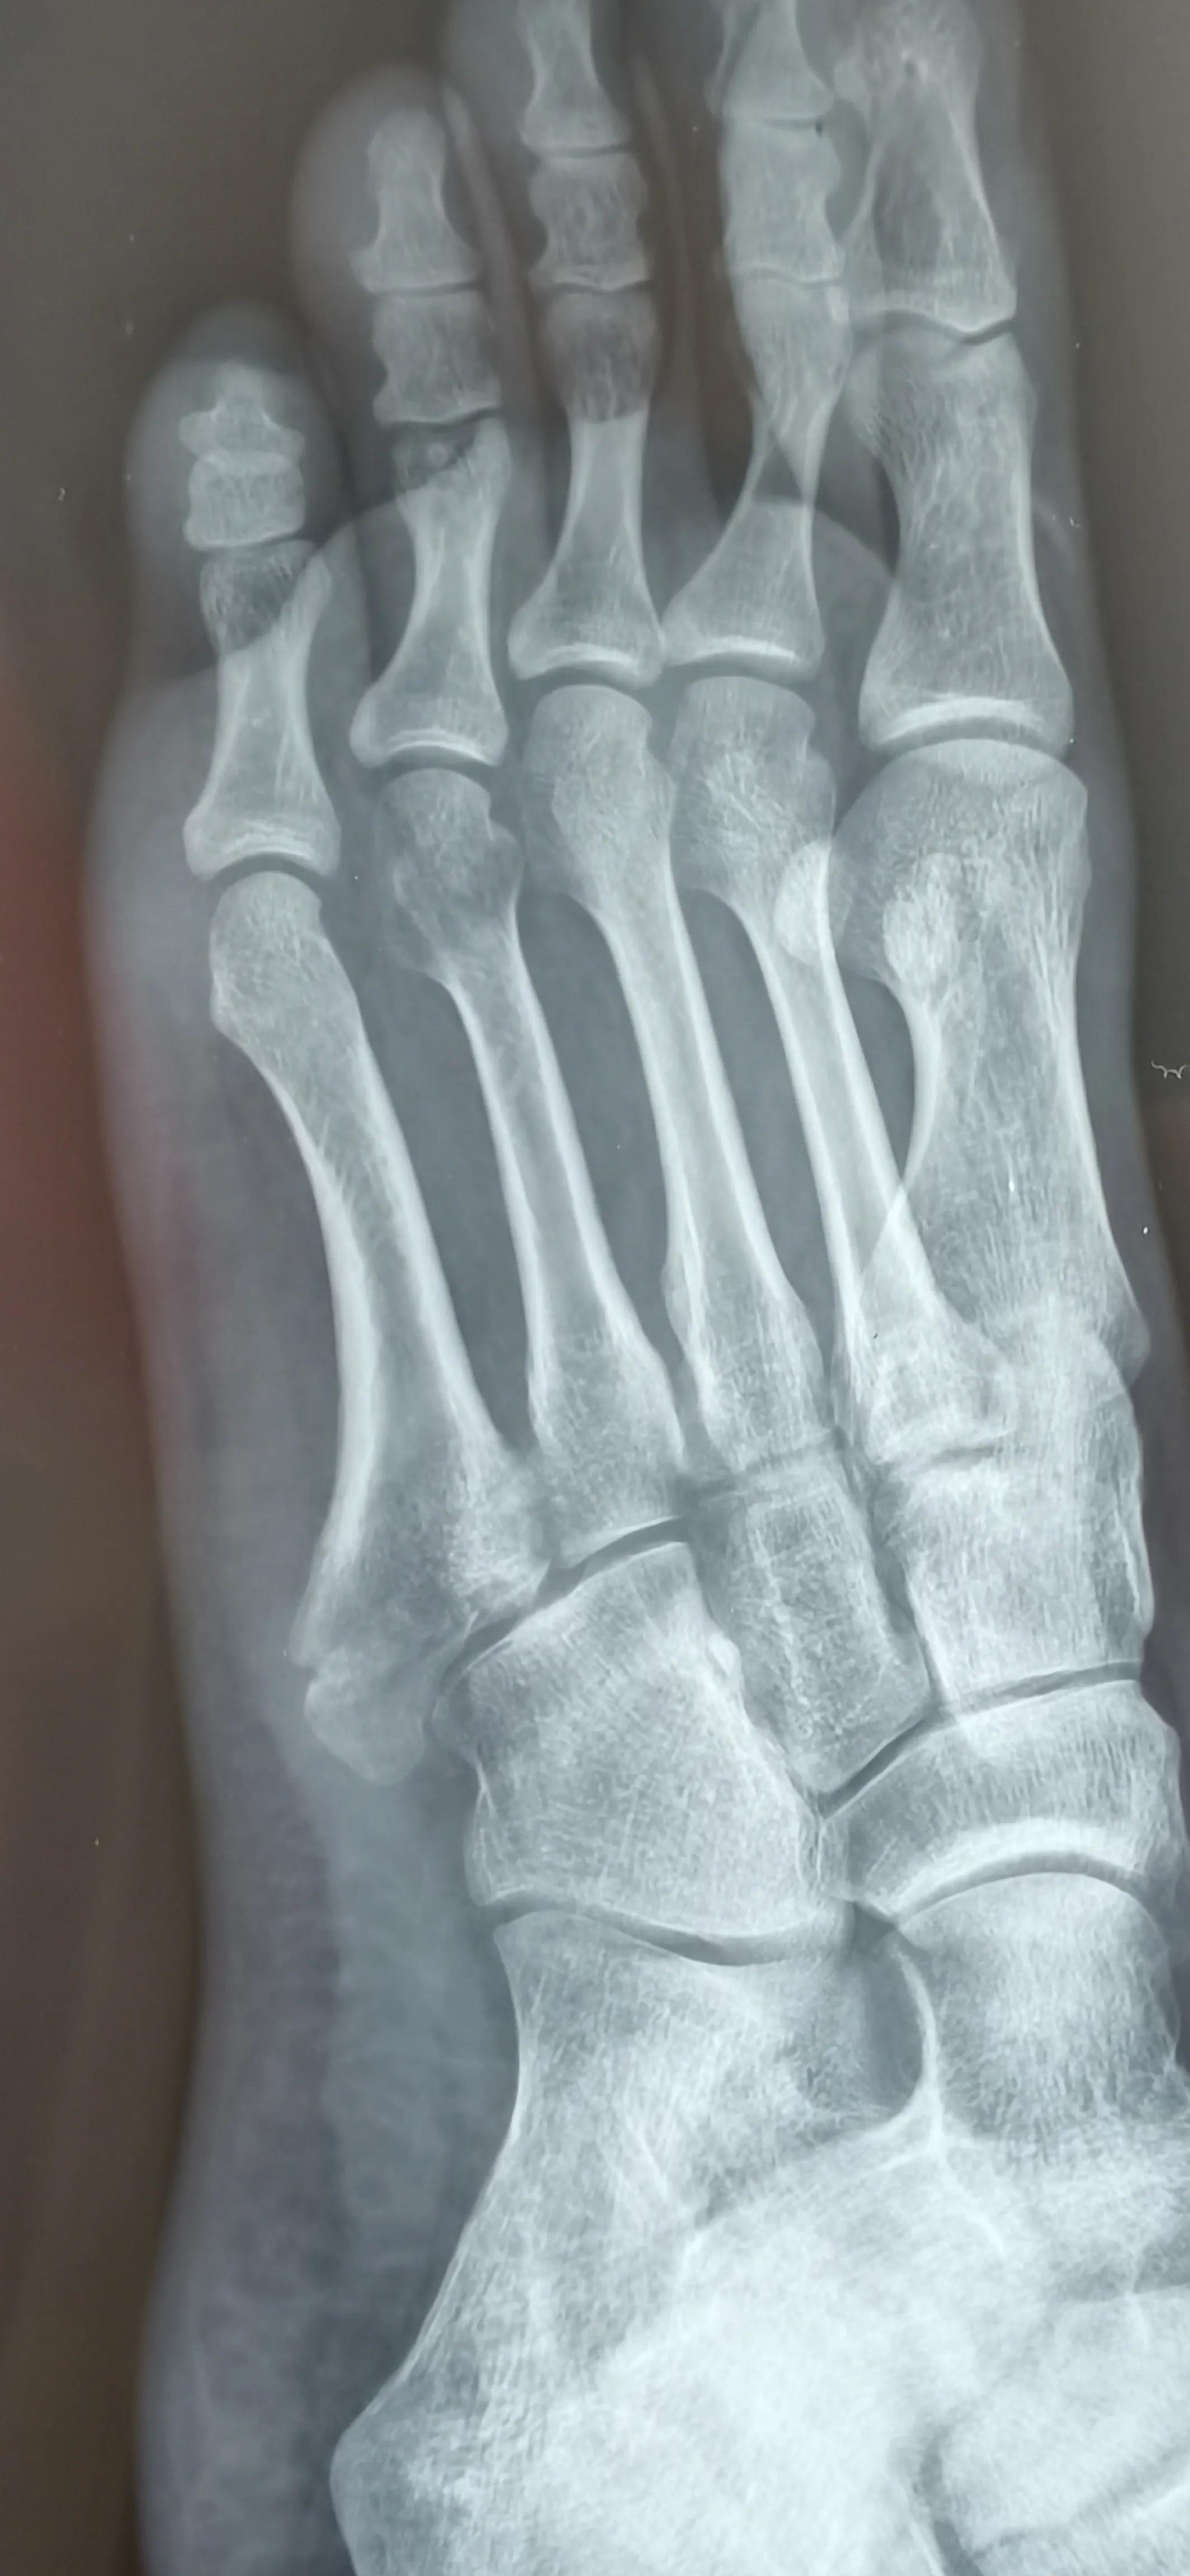

7月底拍了一个CT,愈合不明显,原来第四跖骨也有骨裂,之前都没发现,所以一定要去好医院,好医院器材好,医生经验丰富诊断准确水平高,态度也很有耐心很负责